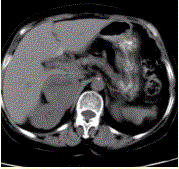

问题 患者男,41岁,发作性头晕、恶心、面色苍白伴高血压半年,入院观察,当时测血压180/80mmHg;上腹部CT示:右侧肾上腺区有直径为5cm圆形稍高密度影,边界清晰,内部密度不均(下图)。 对该患者的治疗预后,阐述错误的是

选项 A.该病大多数为良性,手术切除可以根治 B.手术治疗前应采用α受体阻断药使血压下降,一般应用不少于1周 C.该病在手术切除过程中具有一定危险性,可出现血压骤升和(或)心律失常 D.病变切除术后1周,血压仍可偏高 E.病变为恶性的患者治疗困难,对放疗和化疗不敏感

答案 B